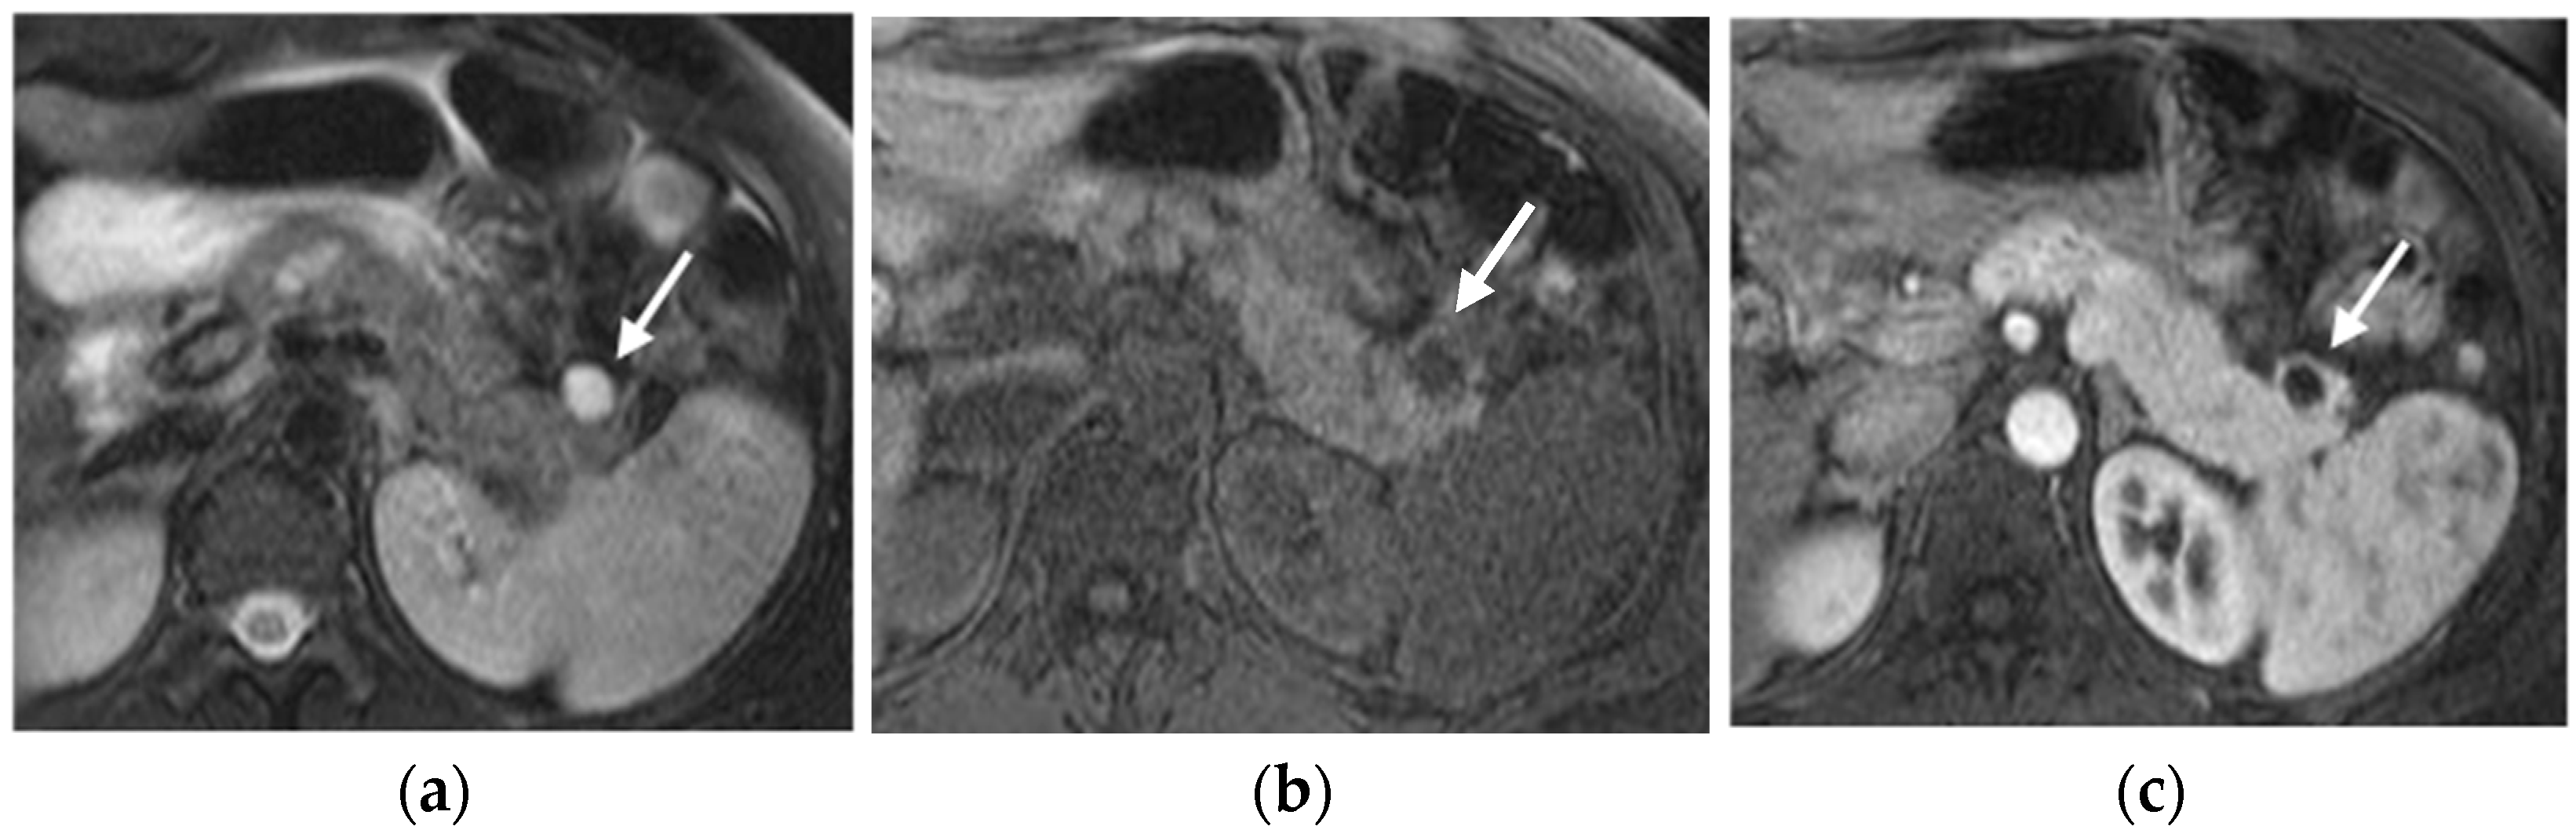

MRI

Nuclear Medicine

- Khanna, L.; Prasad, S.R.; Sunnapwar, A.; Kondapaneni, S.; Dasyam, A.; Tammisetti, V.S.; Salman, U.; Nazarullah, A.; Katabathina, V.S. Pancreatic Neuroendocrine Neoplasms: 2020 Update on Pathologic and Imaging Findings and Classification. Radiographics 2020, 40, 1240–1262. [Google Scholar] [CrossRef] [PubMed]

- Bauckneht, M.; Albano, D.; Annunziata, S.; Santo, G.; Guglielmo, P.; Frantellizzi, V.; Branca, A.; Ferrari, C.; Vento, A.; Mirabile, A.; et al. Somatostatin Receptor PET/CT Imaging for the Detection and Staging of Pancreatic NET: A Systematic Review and Meta-Analysis. Diagnostics 2020, 10, 598. [Google Scholar] [CrossRef]